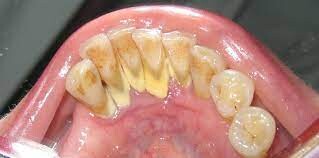

When plaque builds up in your mouth, it can turn into an even greater dental health threat: calculus. This formation, also known as tartar, is a calcified mass that adheres to your teeth. Calculus is classified as either supragingival or subgingival, depending on its location on your teeth. If left unremoved, subgingival calculus can lead to gum disease and tooth loss.

An article published in the International Journal of Dental and Health Sciences (IJDHS) explains that plaque, which is a sticky film of bacteria that constantly forms on your teeth, can mineralize due to the exchange of calcium and phosphate ions present in your saliva. This process is what creates calculus, a hard mass of bacteria stuck to your tooth surfaces.

Plaque can harden into calculus in as little as four to eight hours. The average length of time for mineralization, however, is 10 to 12 days. Calcification times can vary from person to person, depending on their salivary pH and the amount of calcium and other substances in their saliva. Once calculus forms, it then attracts more plaque, which in time can become another layer of calcified material.

Characteristics of Subgingival Calculus

Tartar that accumulates on your teeth above the gumline and is easily seen by your dentist or dental hygienist is called supragingival calculus, according to the IJDHS article. But the tartar that forms below the gumline — and is therefore not immediately visible — is known as subgingival calculus. This type of calculus is usually dark brown to greenish black in color and can be detected with a dental instrument called an explorer.

It's important to note that, while you can clean plaque off your teeth with brushing and flossing, hard tartar can only be removed by a professional cleaning, explains the American Academy of Periodontology (AAP). Your dentist or dental hygienist uses special instruments that are designed to remove the calculus.

Preventing Calculus Formation

Since plaque is what forms tartar, preventing calculus involves cleaning plaque off your teeth regularly to prevent mineralization. This is why it's important to maintain a good oral care routine at home. Be sure to brush your teeth twice a day and floss daily. Using an antimicrobial mouthrinse can also help to reduce the amount of bacteria in your mouth. In addition, you should visit your dentist every six months for dental cleanings. At these cleanings, your dentist or dental hygienist will remove any tartar to prevent inflammation and gum disease.

While subgingival calculus can cause serious dental complications, it's one battle you can win if you keep up with good dental health habits.